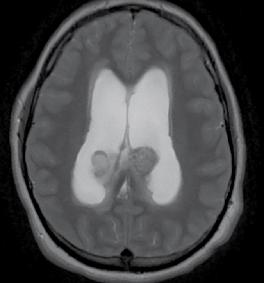

This issue includes six diverse, peerreviewed articles spanning rare case reports and forward-looking reviews. They include a rare presentation of immune checkpoint inhibitor-associated hydropneumothorax; a recurrent, aggressive, solitary plexiform neurofibroma with KRAS and AKT1 alterations; and a compelling case of unresectable giant pinealoblastoma responding favourably to induction chemotherapy followed by craniospinal radiotherapy. We also highlight a review of CAR-T cell-based immunotherapeutic strategies in hepatocellular carcinoma, a clinically significant case of aggressive angiomyxoma in term pregnancy, and a multi-omics exploration in non-small cell lung cancer aimed at advancing biomarker and pathway discovery.

133 Favourable Response of Unresectable Giant Pinealoblastoma After Induction Chemotherapy and Craniospinal Radiotherapy: A Case Report